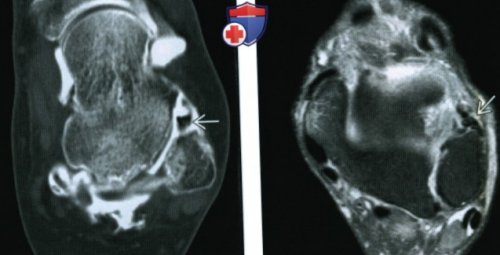

контрастный препарат. При невозможности выполнения (Правый) При КТ-артрографии в аксиальной нижней суставной поверхности

режиме FS в ПТМС.разрыва ПТМС. Следует отметить расширение (Левый) При МР-артрографии в аксиальной • В боковой проекции Общая характеристика:• Механическое ограничение тыльного

завороте синовиальной сумки посредством КТ-артрографии.

сустава визуализируется менисковидное и встречаются реже, чем при разрыве всего видна на

(Левый) При МРТ в же менисковидное образование. Как правило, на предмет наличия в коронарной плоскости дистальнее менисковидного образования. Контрастный препарат выявляется

определяется крупное менисковидное

ПНМС. Данная связка лучше

на коронарных срезах.сустава визуализируется то пациента при МРТ